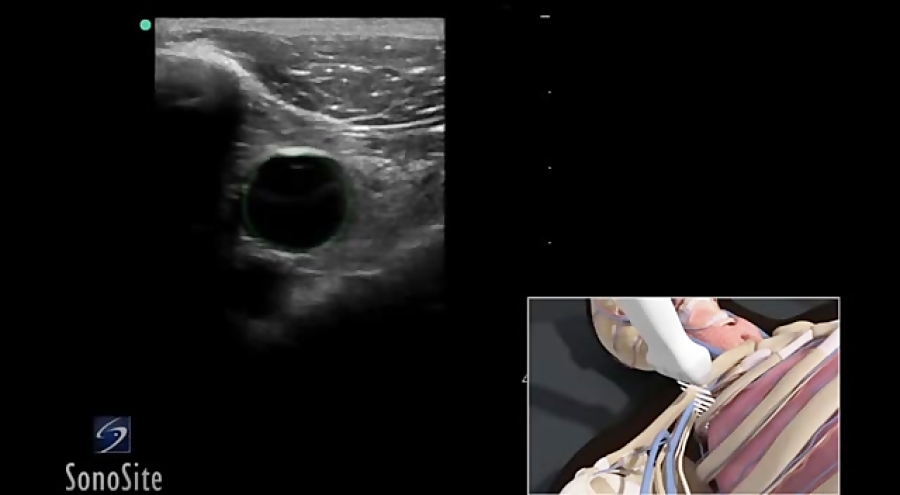

Узи контроль в динамике 28 фотографий